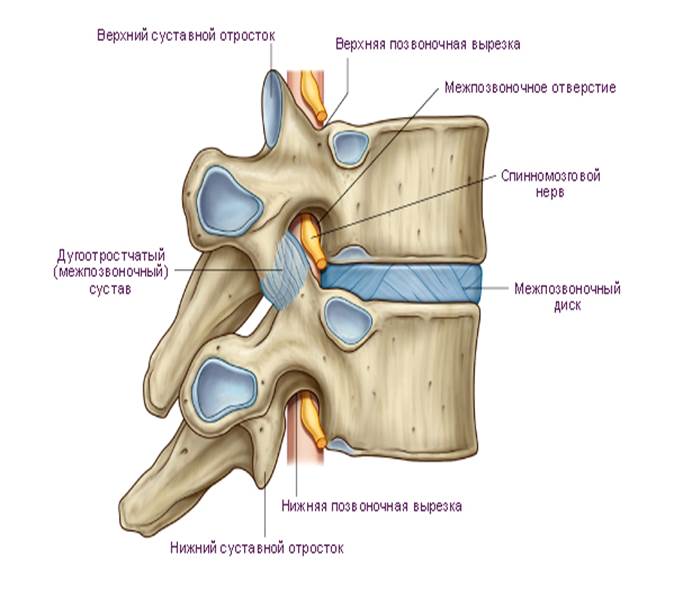

Структура и анатомия синдесмоза: научные иллюстрации